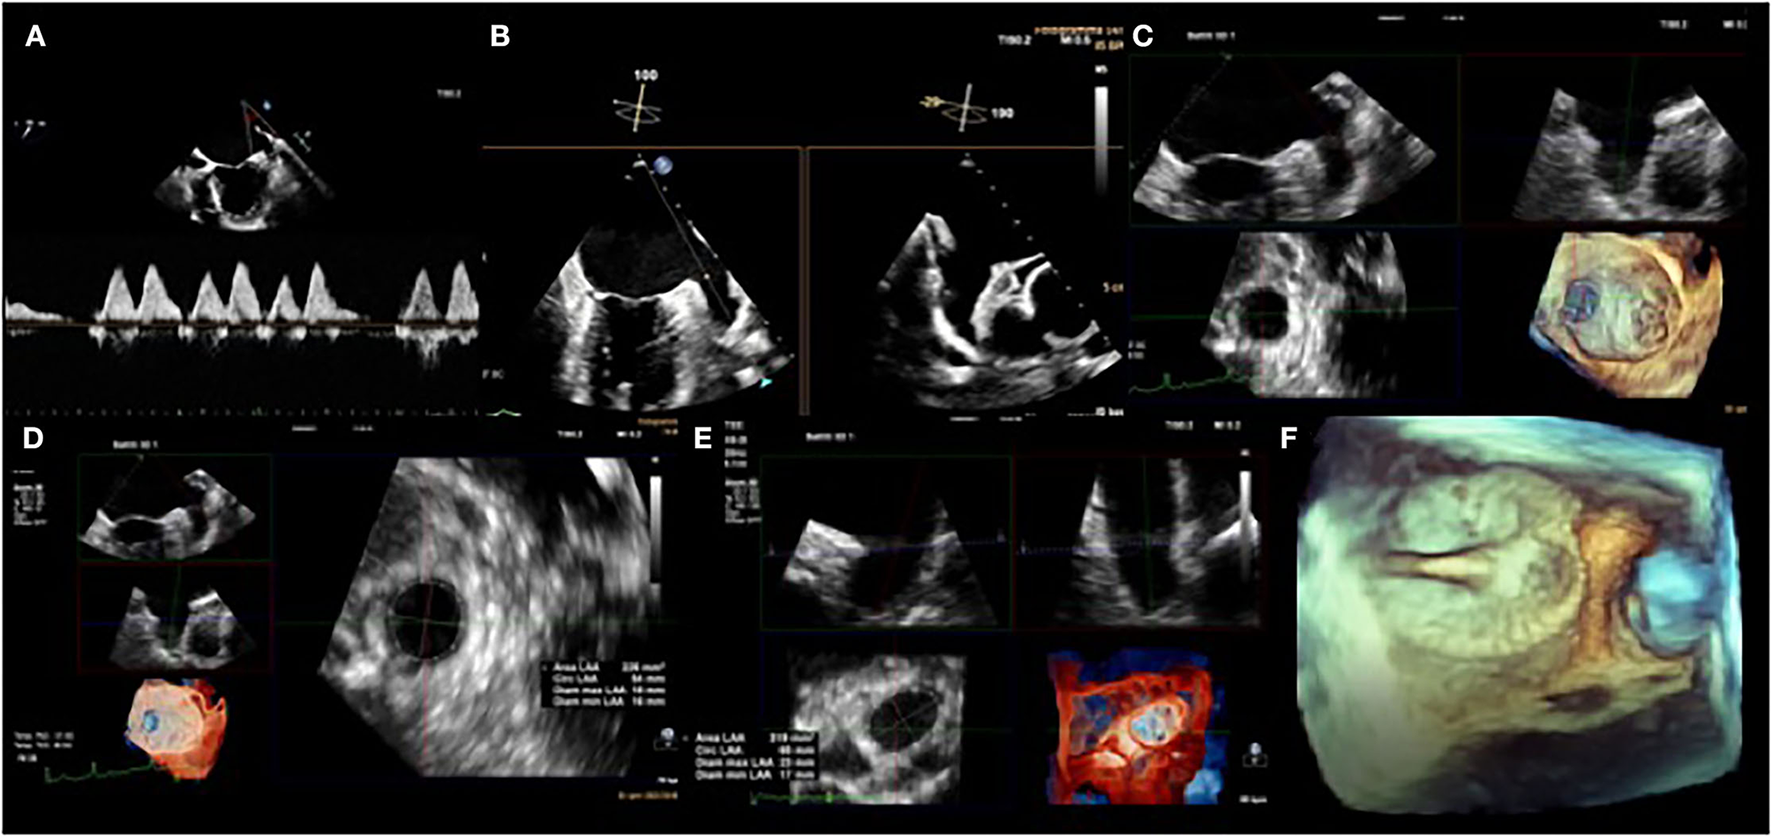

Left Atrial Appendage (LAA) is mainly responsible for the formation of a thrombus that can cause strokes by embolization of the cerebral circulation (3). LAA is a structure derived from the primordial left atrium (LA), which develops during the third to sixth week of fetal cardiac development from the pulmonary venous bud and it has unique physiological characteristics (25). First of all, LAA is more compliant than the left atrium and has an important role in LA decompression during overload. The occlusion of LAA determined an improvement in the LA reservoir and conduit function. Moreover, LAA has an endocrine role. It accounts for the production of atrial natriuretic peptides (ANP) that contribute to natriuresis and diuresis. The distension of LAA is directly correlated with the production of ANP rather than elevation in the LA pressure or distension of the body of LA. For this reason, LAA closure can downregulate Renin-Angiotensin-Aldosterone System and Adrenergic Input (26). There are several morphological LAA classifications. The most commonly adopted one consists of four shapes: chicken-wing (~48%; presence of a significant bend), windsock (~19%; single dominant lobe without a significant bend), cactus (~30%; dominant central lobe with multiple secondary lobes), and cauliflower (~3%; short LAA without a dominant lobe that branches into several lobes) (27). The shape of the LAA may affect stroke risk. In particular, the presence of extensive trabeculations is correlated to higher risk. Furthermore, the LAA shape can increase the technical challenge for percutaneous LAA closure. Therefore, imaging is essential to pre-plan equipment selection and implantation strategy, to guide procedural device implantation, and also for device surveillance post implantation. The transesophageal echocardiography 2D (2D TOE) is routinely used in assessing LAA morphology, and recent 3D innovations such as multiplanar reconstruction (3D TOE MPR) and 3D TOE TrueView Glass rendering (Figure 2), have increased its accuracy. However, the gold standard in defining the morphology of the LAA remains the computed tomography (CT). LAA occlusion provides an alternative to oral anticoagulation for thromboembolic risk reduction in patients with nonvalvular atrial fibrillation (28). The earliest study was made by Madden et al. in 1948, which showed that the LAA was a source of thrombus formation in patients with AF and that its removal could prevent systemic thromboembolism (29). Subsequently, surgeons started to exclude progressively, the LAA during mitral valve intervention, in patients with AF. Over the years, many devise has been developed for the closure of the LAA by percutaneous interventional techniques. The first device designed for percutaneous LAA occlusion was the PLAATO device (Appriva Medical, Sunnyvale, California) (30). The device is made by a self-expanding nitinol cage covered by a polytetrafluoroethylene membrane. Despite the promising results, this device was taken off the market in 2016 (31). Currently, many percutaneous LAA closure devices have obtained CE mark. Watchman (Boston Scientific, Marlborough, MA, USA) and the Amplatzer Cardiac Plug (ACP) (Abbott, St Paul, MN, USA) are the most commonly used devices for mechanical orifice obstruction, and the Lariat device (SentreHEART, Redwood City, CA, USA) for epicardial suture ligation. The Watchman device is approved in many countries worldwide and is the only device studied in randomized trials, as well as in multicenter prospective non-randomized studies. The PROTECT AF (Watchman Left Atrial Appendage Closure Device for Embolic Protection in Patients with atrial Fibrillation) trial, a multicenter prospective RCT, established that the percutaneous LAA closure device was non-inferior to warfarin for the combined primary efficacy endpoint of cardiovascular mortality, all-cause mortality, and systemic thromboembolism (32). The PREVAIL (Prospective Randomized Evaluation of the Watchman Left Atrial Appendage Closure Device in Patients With Atrial Fibrillation vs. Long Term Warfarin Therapy) trial, was conducted to assess the safety and efficacy of LAA occlusion raised from the PROTECT AF study. The study concluded that LAA occlusion was non-inferior to warfarin for ischemic stroke prevention (33). For ACP and its second-generation, Amulet, multiple retrospective and prospective registries have reported successful device implantation in 95–100% of patients, with a low rate of major periprocedural adverse events. A recently published, industry-initiated, large, randomized, multi-center, trial (Amulet IDE trial), evaluating the safety and effectiveness of the Amulet occluder compared with the Watchman™ device, has shown that the Amulet occluder was non-inferior to safety and effectiveness of stroke prevention compared with the Watchman device (34). In light of the results of these trials, ESC guidelines suggest LAA closure, for stroke prevention, in patients with AF and contraindications for long-term anticoagulant treatment, e.g., intracranial bleeding without a reversible cause (class of recommendation IIb, level of evidence B) (35).

Figure 2

Transesophageal echocardiogram. Left atrial appendage (LAA) flow velocity pattern by pulsed-wave Doppler (A). 2D TEE biplane LAA assessment. Note how the appearance of the appendage varies in the different views (B). 3D TEE evaluation of the LAA landing zone (C), with post-processing analysis measurements of the diameters and the area of the LAA (D,E). 3D colorized depth map of LAA occluder device using peri-operative TEE (F).